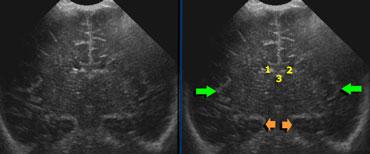

1+2 = nang tiêu mầm và giả nang, 3 = nhuyễn chất trắng quanh não thất dạng nang, 4 = nang do nhồi máu tĩnh mạch

Các loại nang

Khi phát hiện nang quanh não thất bên, điều quan trọng là phải xác định vị trí của chúng so với phần trên của não thất bên (xem hình).

- 1+2 = Nang tiêu mầm và Giả nang nằm dưới hoặc ngang mức phần trên của não thất bên.

- 3 = Nhuyễn chất trắng quanh não thất dạng nang (Cystic periventricular leukomalacia) chủ yếu nằm trên mức này.

- 4 = Nang do nhồi máu tĩnh mạch có kích thước lớn và có thể nằm trên, ngang hoặc dưới mức này.

Đo kích thước não thất

Việc đo kích thước hệ thống não thất cần được thực hiện trên một mặt phẳng siêu âm chuẩn, dễ tái lập.

Sử dụng mặt cắt vành (coronal) qua các não thất bên, ở vị trí ngay phía sau lỗ Monro.

Trên mặt cắt này, sẽ thấy 3 chấm tăng âm đại diện cho đám rối mạch mạc trong các não thất bên và ở trần não thất ba.

Ngoài ra, cần thấy được hình ảnh đối xứng của rãnh Sylvius ở cả hai bên và hồi hải mã (mũi tên màu xanh lá và màu cam).